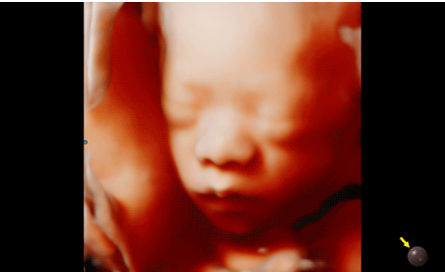

3D/4D成像方面,Hera i 10通過(guò)結(jié)合先進(jìn)的圖像渲染技術(shù),著重加強(qiáng)了邊緣和小結(jié)構(gòu)的可視化能力。